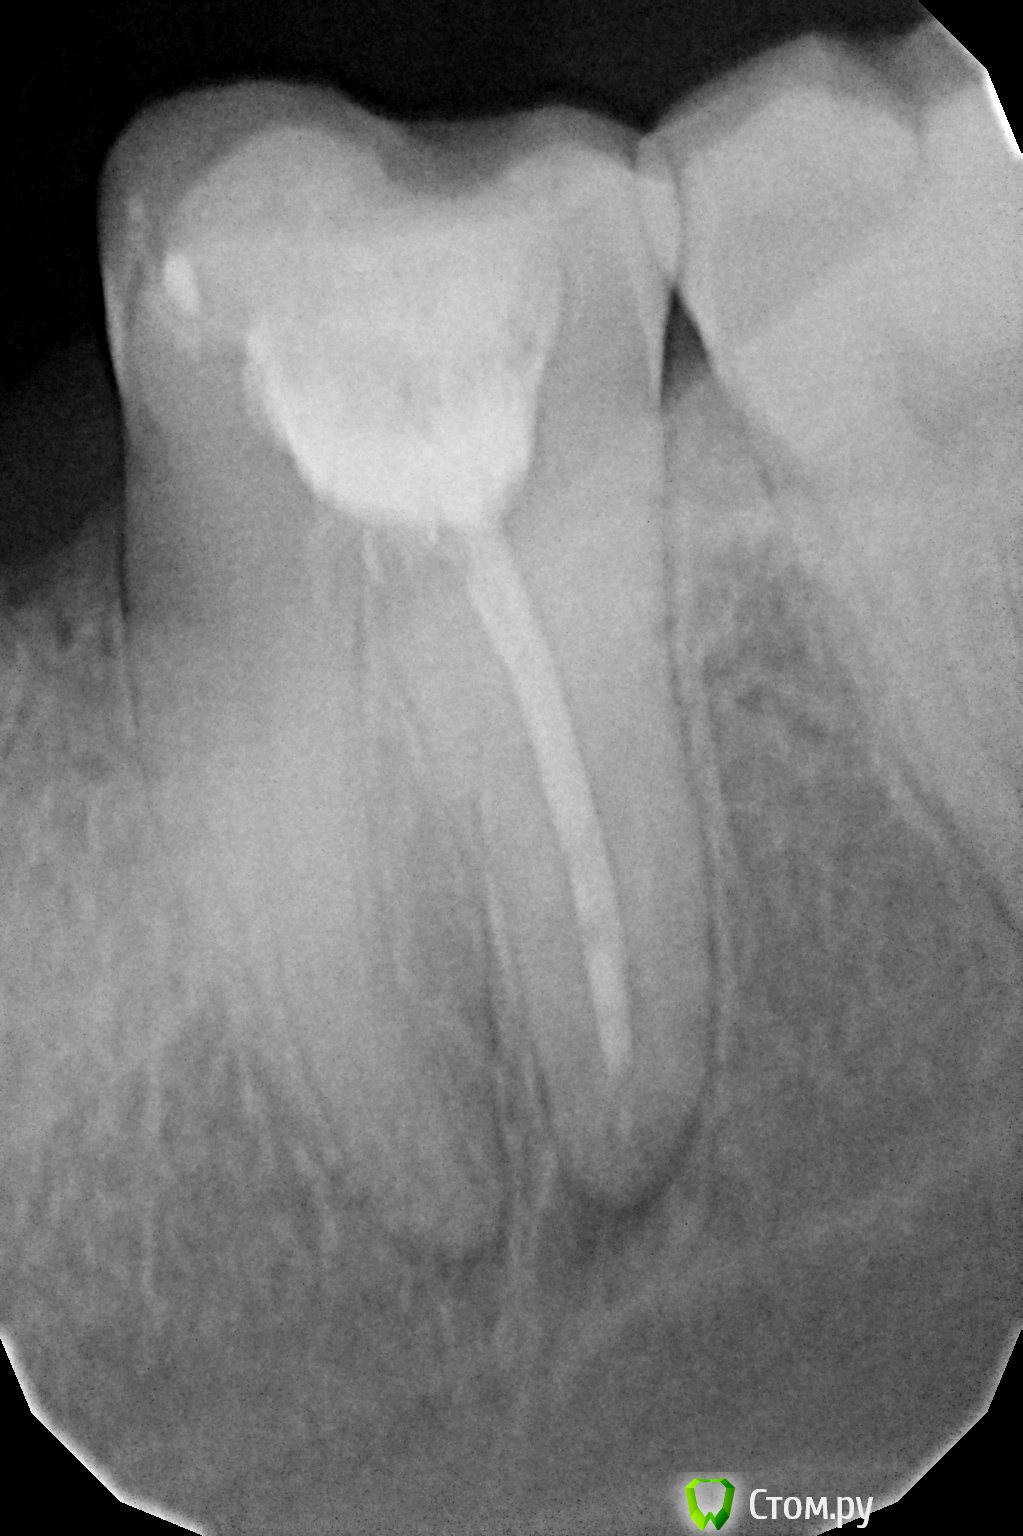

Pesto325 Опубликовано 26 октября, 2014 Поделиться Опубликовано 26 октября, 2014 дорогие стоматологи,помогите решить проблему,мне запломбировали зуб боль стояла 3 дня на 4 стала стихать по чуть чуть,пошел сделал снимок на нем на конце корня есть небольшое серое пятно,боюсь не киста ли там у меня ,что посоветуете предпринять? Заранее большое спасибо!!! Ссылка на комментарий

Pesto325 Опубликовано 26 октября, 2014 Автор Поделиться Опубликовано 26 октября, 2014 Требуется повторное лечение корневых каналов, ищите стоматолога-эндодонтистя не могу понять снизу под корнем это киста? Ссылка на комментарий

red_butler Опубликовано 26 октября, 2014 Поделиться Опубликовано 26 октября, 2014 я не могу понять снизу под корнем это киста?Это гранулема Ссылка на комментарий